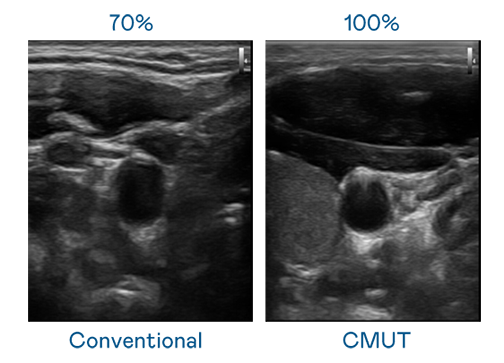

CMUT ¼¼ÊõÊÇÒ»ÖÖÓõçÈÝʽ΢»úµçÔª¼þÀ´²úÉú³¬Òô²¨Ñ¶ºÅµÄ¼¼Êõ¡£Ó봫ͳ PZT ѹµçʽ¼¼ÊõÏà±È£¬CMUT Ƶ¿íÔö¼Ó 30%£¬¸ü¿íƵµÄ³¬Òô²¨Ñ¶ºÅÈÃÓ°Ïñ½âÎö¶È´ó·ùÌáÉý£¬ÊÇʵÏÖ¸ßÓ°ÏñÆ·ÖÊÒ½ÁƳ¬Òô²¨É¨Ãè¡¢´Ù½ø¾«×¼Ò½ÁÆ·¢Õ¹µÄ¹Ø¼ü¼¼Êõ¡£

³¬Òô²¨Ó°ÏñµÄ½âÎö¶È¸ßµÍ£¬Ê×ÏÈÈ¡¾öÓÚ̽ͷÄÜ·¢³öµÄѶºÅƵ¿í¡£Æ´²«ÌåÓý¹ÙÍø CMUT ¿ÉÌṩ¸ßÇåÎúµÄ³¬Òô²¨Ñ¶ºÅ£¬Ìṩ¸ßƵ¿í¡¢¸ßÁéÃô¶È¡¢Ó°ÏñÎÆÀíϸ½Ú¸ü¸ßµÄ³¬Òô²¨Ó°Ïñ£¬ÐÖúÒ½»¤ÈËÔ±Ëõ¶ÌÓ°ÏñÅжÁʱ¼ä¼°ÀûÓþ«×¼µÄÒ½ÁÆÓ°Ïñ½øÐÐÕï¶Ï¡£